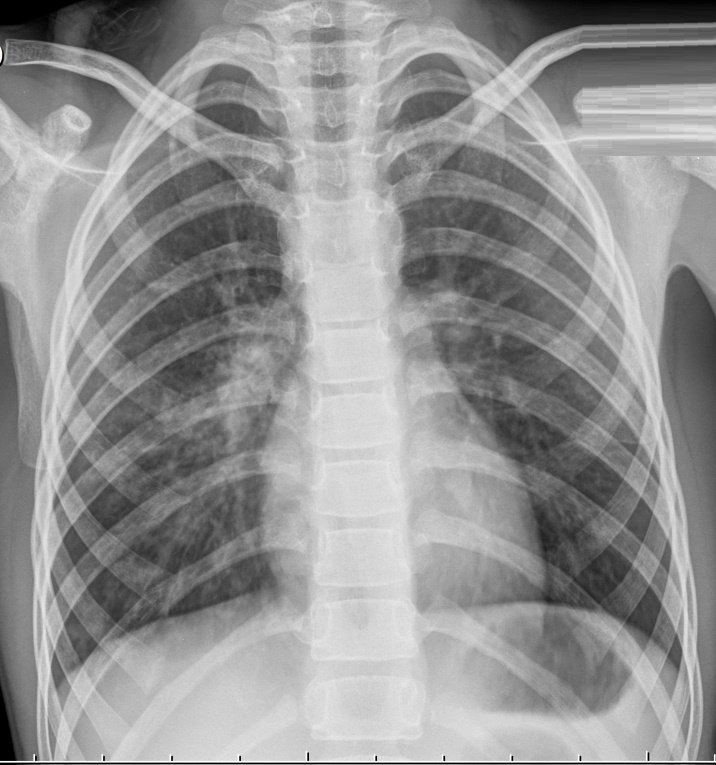

Первый признак пневмонии на рентгеновском снимке – появление очагов затемнения с неровными контурами в разных частях легкого, которые могут иметь разный размер, от 3-4-х до 12 мм.

Фото3

Тени различают по внешнему виду (круглые, овальные кольцевидные) и интенсивности окраски – чем темнее пятно, тем сильнее выражен патологический процесс.

При поражении лимфатических узлов и нарушении кровоснабжения органа могут наблюдаться изменения корней легких, а если болезнь затронула плевру – нарушение в рисунке куполов диафрагмы. В остальном проявления пневмонии зависят от стадии, формы и клинических особенностей заболевания:

1. Очаговая форма. На рентгене отображаются небольшие (1-1,5 см) тени со слабой или умеренной интенсивностью окраски, неоднородной структурой и нечеткими границами. Очаги поражения могут быть единичными или множественными, а в некоторых случаях они сливаются в одно большое пятно. Корни легких расширены, причем нарушения нормального рисунка органа могут сохраняться в течение нескольких дней после выздоровления.

2. Крупозная пневмония. Наблюдаются изменения нормального легочного рисунка, жидкость в полости плевры, признаки инфильтрации одной из долей легкого, расширение корней. По мере развития воспалительного процесса выраженность изменений и интенсивность окраски затемнений усиливается.

3. Интерстициальная форма. На снимке заметно уплотнение корней легких и другие изменения, которые формируют выраженный рисунок, напоминающий ветви дерева.

4. Абсцедирующая пневмония. Проявляется обширным затемнением пораженной области, признаками утолщения плевры и наличием полостей разного размера, наполненных жидкостью.

5. Аспирационная форма. Рентген характеризуется треугольными пятнами с однородной структурой, светлыми очагами и приподнятой диафрагмой.